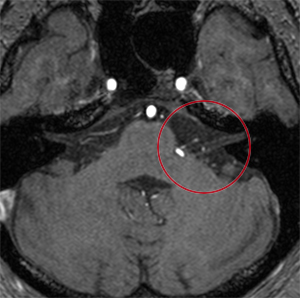

顔面痙攣・三叉神経痛

顔面痙攣・三叉神経痛についてはMRIで神経に血管の圧迫があるかをまず確かめます。症状を緩和する薬物療法でなく根治的治療を希望される場合は、神経血管減圧術を行います。治療効果や安全性が高まるような手技を心掛けています。

顔面痙攣で顔面神経に血管(白)が圧迫

立体的画像